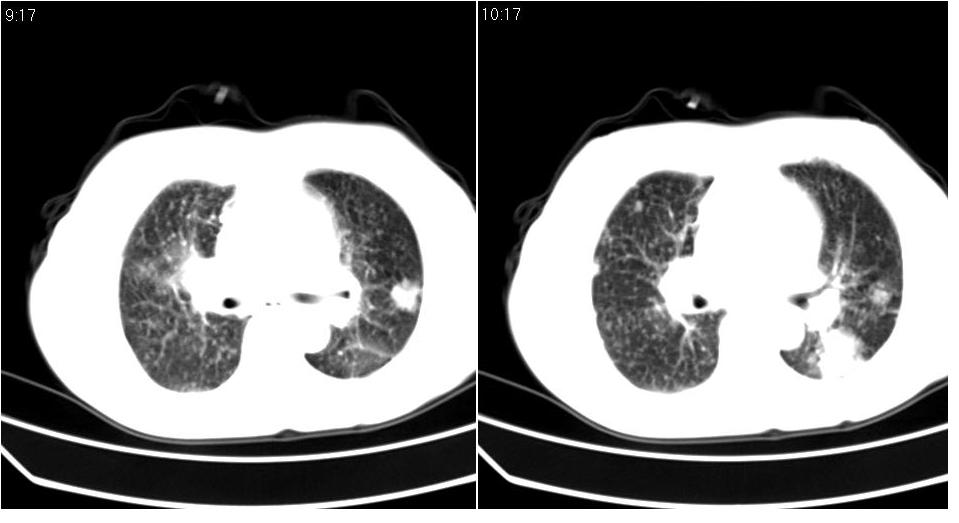

标题: CT16839:胸部CT平扫

女 50岁,在其他医院确诊肺癌.

支持 右肺上叶肺癌并两肺及纵隔转移。